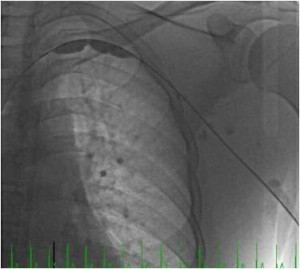

Thrombolysis

Several series show that early treatment with thrombolysis has better success rates than later treatment. Obviously, I mean local, catheter directed, thrombolysis. However, without complimentary treatment recurrence rates are high, as shown in a prospectively collected cohort treated by either thrombolysis and surgery or thrombolysis alone. In this cohort recurrence was especially high in young patients who did not have surgery (23%), while surgical treatment achieved a high long-term success rate (93%). However, there is another way to look at the same data. Many of the patients who received thrombolysis alone did well in the long-term.

Many claim that stents are not suitable for the thoracic outlet becuase of elevated compression forces they would need to withstand, and therefore the high risk of stent failure and fracture. Those opposed to surgery state the risks involved and the unknown added benefit.